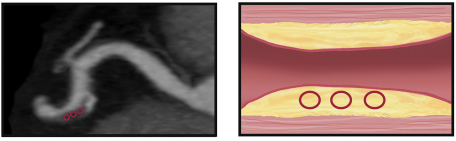

Napkin ring sign

Spotty calcifications